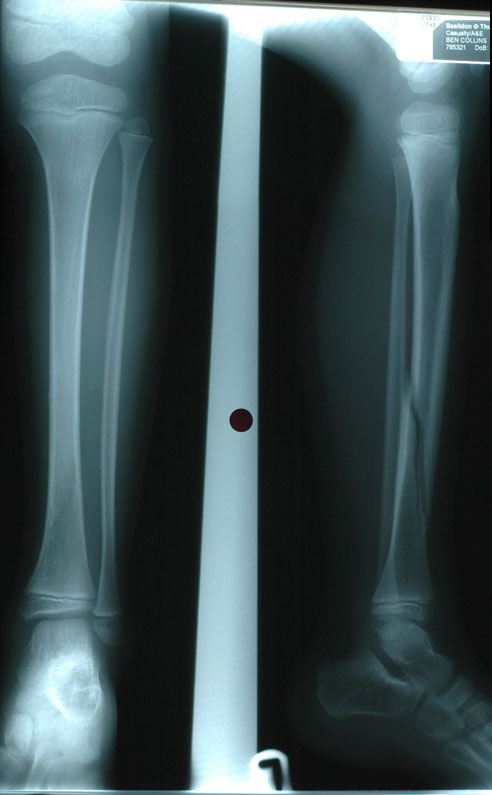

Ben's Broken Leg

On Sunday, 12th June, Ben broke his leg whilst going down a big 'tube' slide. He was a bit nervous but I said, "What could possibly go wrong..." He's now going around telling everyone that his naughty Dad broke his leg by forcing him down a slide!